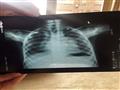

في محافظة الدقهلية، عرض زكريا ابنه على عشرات الأطباء "عمل الإشاعات المقطعية، لكن محدش عرف يشخصه.. اللي يقولي حساسية على الصدر، واللي يقولي عضم الصدر ضاغط على الرئتين، واللي يقولي ورم في القصبة الهوائية والعمود الفقري.. دوخت بالواد وحالته بتسوء".

في مركز علاجات القلب والأوعية الدموية بإحدى المستشفيات الخاصة بالقاهرة، ذكر التقرير الطبي، الصادر في يناير الماضي، والذي حصل مصراوي على صورة منه، أن المريض "دخل المستشفى وهو يعاني من فشل تنفسي حاد بالأكسجين، وتضخم بالغدد الليمفاوية بالحيزوم، وقد خضع لعملية جراحية لأخذ عينة من الرئة والغدد الليمفاوية وورم مجاور للعمود الفقري، ولا زال المريض في حاجة للأكسجين بصورة مستمرة ولا يتحمل فصله عنه لفترات قصيرة".

وضع زكريا العينات التي تم أخذها من رئة طفله لدى مكتب خاص، يتكفل هو بإرسالها إلى معمل في بريطانيا "عشان مفيش حد خبير في قراءة الأنسجة في مصر"، عادت النتيجة إلى الأب ومفاداها أن "إسلام محتاج زرع رئة"، عزم زكريا على إتمام الأمر، لكن "عرفت أن زرع الأنسجة مش موجود غير في السعودية وبريطانيا وأمريكا واليابان".

لجأ الأب إلى المجالس الطبية المتخصصة، والتابعة لوزارة الصحة، ليجدوا له حلًا، لكن خرج عنها خطاب إداري، مُوقع من الدكتور عماد خيري كاظم، مدير الإدارة العامة للمجاللس الطبية المتخصصة، ومختوم بالنسر، حصل مصراوي على صورة منه، يشير نصه إلى: "ترى لجنة القلب والصدر بجلسة 24 مارس 2018، أنه بعد مراجعة التقرير والفحوصات الخاصة بالمريض، وجد أنه يحتاج إلى جراحة لزرع رئة، وهي تجري بالخارج فقط لأهل البلد أو البلاد التي بينها اتفاقية لتبادل الأعضاء من مرضى بموت جزع المخ".

واستكمل الخطاب كلماته: "وحيث أنه لا يوجد اتفاقية بين مصر ودول أخرى لتبادل الأعضاء، فأن الفرصة الوحيدة هي عمل جراحة لزرع الرئة من اثنين متبرعين أحياء (أخذ فص من الرئة من كل منهما) من نفس فصيلة المريض ودرجة قرابة حتى الرابعة، مع عمل الفحوص اللازمة لكل منهما وتحديد إمكانية تبرعهما، على أن يكون السن بين 18-50 عامًا".